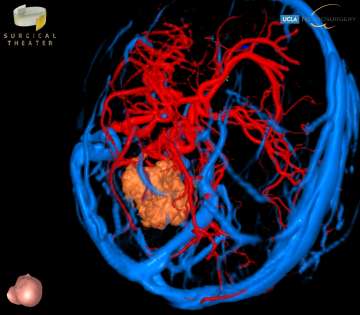

Medical scan shows a brain's blood vessels in blue and red, with a beige tumor highlighted in the center. Click image to enlarge

Medulloblastomas are the most common malignant brain tumors found in children. Between 250 and 500 children under the age of 16 are diagnosed with medulloblastoma each year in the United States, and it accounts for nearly 20% of all childhood brain tumors. Presenting symptoms are usually from obstructive hydrocephalus, and typically include headaches, nausea and vomitting, clumsiness, visual changes, and issues with coordination. Surgery is the first step in treating medulloblastoma, followed by chemotherapy and/or radiation therapy. The survival rates in children depend on the surgeon’s ability to safely and completely remove the tumor, and the sub-type of medulloblastoma. With optimal care, long-term survival rates can be better than 80%.